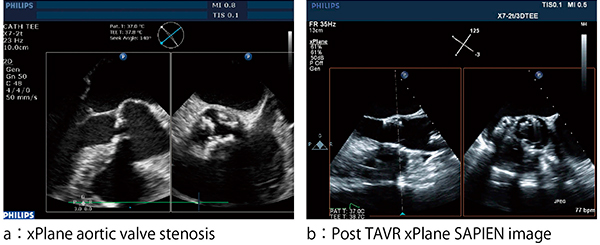

また,Live 3D TEE Imageだからこそ可能となる任意の2方向を一度に観察可能なxPlane Imageも,現在SHD治療に多く使用されており,この機能の重要性は臨床現場からも高い評価を得ている(図5)。

図5 xPlane Imageによる任意の2断面同時表示